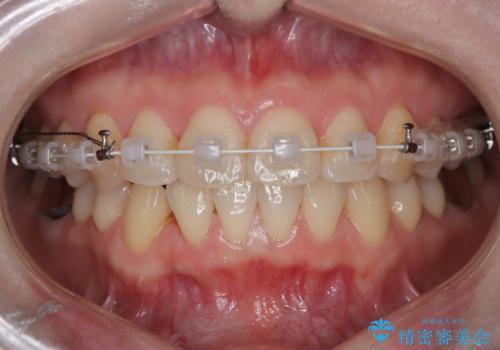

- インビザラインと審美装置

- 前歯の翼状捻転の改善を希望してこられた患者様です。

下顎の叢生はインビザラインで解決することがきましたが、上顎の捻転が完全には改善できなかったため、上顎は途中からワイヤーを用いて治療を行っています。

捻転の改善はインビザラインで苦手とするところですので、うまく治らない場合はワイヤーを提案しています。